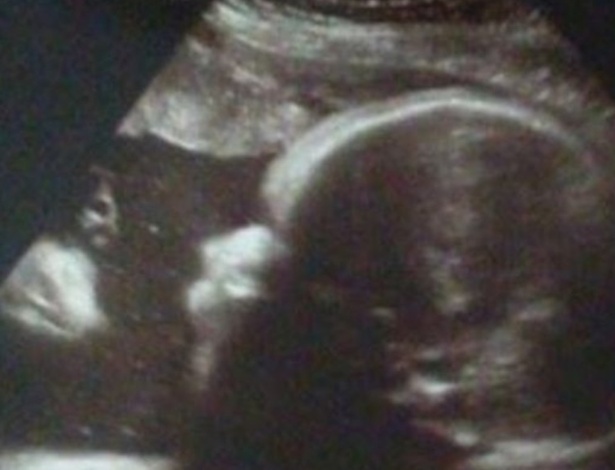

Um casal ficou surpreso após ver a ultrassom do bebê, na Pensilvânia.

De acordo com o site ‘UOL’, eles não detectaram nenhuma doença, felizmente. Mas, se surpreenderam com uma imagem que parece ser de um homem ao lado do bebê.

A publicação afirma que o casal não é religioso, mas acredita ter visto um homem com uma túnica com espinhos olhando para o bebê. O bebê nasceu saudável na última terça-feira (22).